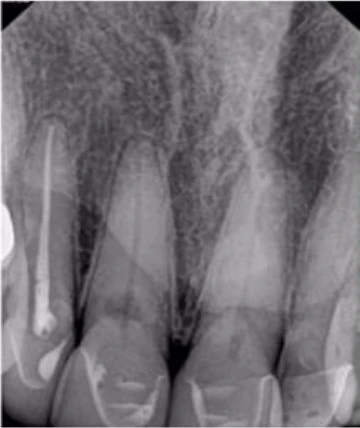

Mẹ tôi có tiền sử chấn thương khi đang chơi tennis với bố vài năm trước đây. Trước đó khi khám ở bác sĩ tổng quát, phim cận chóp hàm dưới gợi ý phải điều trị tủy, bà đến chỗ tôi ngay lập tức. Chất lượng phim cận chóp của chỗ bác sĩ trước không giống của mình, do đó tôi chụp lại một phim khác (Hình 17). Không chỉ thấy tổn thương nội tiêu nhỏ ở răng 46 mà còn tổn thương tiêu mở rộng răng 31 và 41 ban đầu khiến tôi nghĩ răng này không còn hy vọng gì và phải nhổ đi làm implant.

Hình 17: Ảnh XQ trước điều trị

Tuy nhiên sau khi chụp 3D, tôi đã có thể thấy mức độ tiêu xương ở lát cắt ngang, đứng dọc, đứng ngang; điều may mắn là nó không vượt ra khỏi phạm vi răng (hình 18 và 19).

Tôi quyết định theo dõi răng 46 và tiến hành điều trị răng 31, 41 bằng Ca(OH)2 (hình 20). 3 tuần sau hẹn bà tới trám bít ống tủy (hình 21). Bà quay lại để tái khám sau 1 năm vào mùa hè 2017. Kết quả điều trị coi như đã thành công, không thấy tiêu xương thêm (Hình 22). Hơn thế, răng 46 không thay đổi tình trạng tiêu. Có phim CBCT giúp theo dõi sự thay đổi về kích thước và mức độ tiêu xương trên răng bệnh nhân qua thời gian. Ngoài ra, CBCT cũng cho biết khi nào không nên điều trị, tôi đã tự tin chỉ cần theo dõi răng 46 từ đó hạn chế điều trị không cần thiết cho chính mẹ mình.